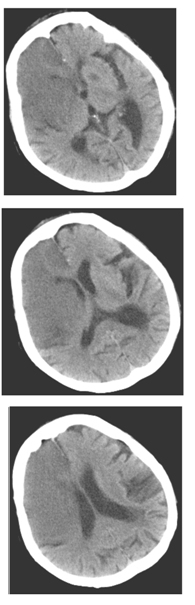

女性,70歲,昏迷,大小便失禁12小時。查體:血壓200/110mmHg,心率約120次/分,體溫37℃。淺昏迷,左側肢體未見自主活動,肌力增高,Babinski征陽性。既往高血壓病史。

6.患者檢查圖像如下,應考慮何種疾病

A.腦膜炎

B.星性細胞瘤

C.腦出血

D.腦動靜脈畸形

E.腦梗塞

F.腦膿腫

7.診斷依據是哪些

A.昏迷,大小便失禁12小時

B.CT顯示右側大腦額、顳葉大片狀均勻低密度灶

C.既往高血壓病史

D.右側側腦室受壓

E.大腦鐮鈣化

F.左側基底節區低密度灶

8.大面積腦梗塞的典型表現包括

A.梗塞區域與該區動脈供血區域一致,呈扇形或楔形,同時累及灰質和白質

B.梗塞發生6h后,可見大腦中動脈水平段條形高密度影,外囊與島葉皮層界限模糊

C.梗塞區腦溝變淺

D.6~24小時部分病灶出現低密度

E.大部分病例24h之后才出現典型的低密度改變

F.增強后病變明顯強化

9.常見的腦梗塞影像學分型包括

A.腔隙性腦梗塞

B.缺血性腦梗塞

C.出血性腦梗塞

D.分水嶺梗塞

E.顱內靜脈及靜脈竇血栓形成

F.腦軟化灶

正確答案:5.E;6.E;7.ABCD;8.ABCDE;9.ABCDE